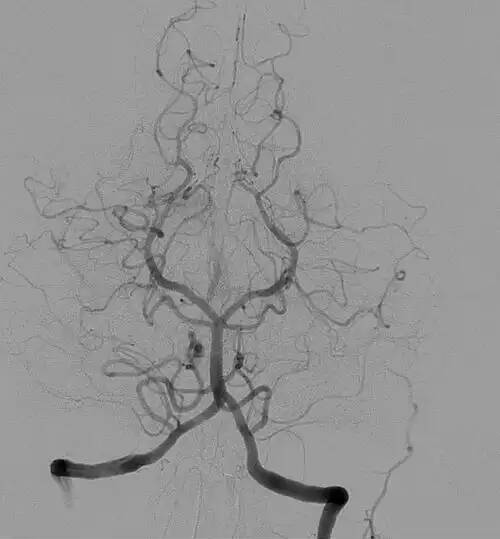

آنژیوگرافی. رگ نگاری یا آنژیوگرافی ( به انگلیسی: angiography ) پرتونگاری از رگ های خونی، پس از پر کردن آن ها از ماده حاجب، برای مشاهده و معاینه دقیق آن ها است این کار روشی برای تشخیص پاتولوژی فضای داخلی رگ های خونی یا لومن است. این روش نخستین بار توسط پزشک پرتغالی آنتونیو اگا مونیش ( به پرتغالی: António Egas Moniz ) برای تشخیص برخی از بیماری مرتبط با سیستم گوارش مانند تومورهای آن به کار گرفته شد. اکنون رادیولوژیست ها و کاردیولوژیست ها با استفاده از این تکنیک جراحی های تهاجمی بسیار ظریفی را در سیستم گردش خونی، به خصوص ورید اجوف تحتانی انجام می دهند. آنژیوگرافی بهترین روش تشخیص بیماران ایسکمیک قلبی است.

آنژیوگرافی روندی است که دقیق ترین اطلاعات ممکن از عروق را تهیه و قبل از عمل در اختیار جراح قرار می دهد. بر پایه این اطلاعات، جراح می تواند برخی از بیماری ها را بدون نیاز به عمل جراحی باز، درمان کند و در صورت نیاز به عمل باز، این اطلاعات، جراح را در انجام سریع و دقیق این امر یاری می رساند. امروزه آنژیوگرافی به منظور تشخیص، به صورت سرپائی از دو طریق کشاله ران و مچ دست انجام می گیرد. ابتدا از طریق یک کاتتر که وارد فضای داخل عروقی شده است و تا مبدأ عروق مورد بررسی هدایت شده است ماده حاجب به ابتدای رگ مورد بررسی تزریق می شود و سپس تصویربرداری رادیوگرافی انجام می شود. عروق دچار تنگی یا اتساع یا انسداد در تصویر کاملاً مشخص هستند. درحقیقت آنژیوگرافی، روش استاندارد طلایی برای تشخیص تنگی ها یا سایر اختلالات عروقی است.

💡 آنژیوگرافی مغزی یک آزمایش تشخیصی است که در آن از اشعه ایکس استفاده می‌کنند. آنژیوگرافی مغزی می‌تواند به پزشک کمک کند تا به بررسی انسداد یا سایر اختلالات در رگ‌های خونی سر و گردن بیمار بپردازد.